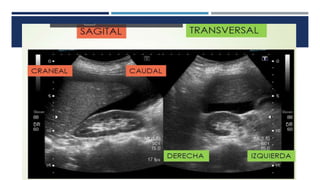

El documento presenta información sobre principios de laboratorio y ayudas diagnósticas para veterinarios. Se enfoca en temas como procedimientos de laboratorio, pruebas de diagnóstico, y herramientas para identificar y tratar enfermedades en animales.